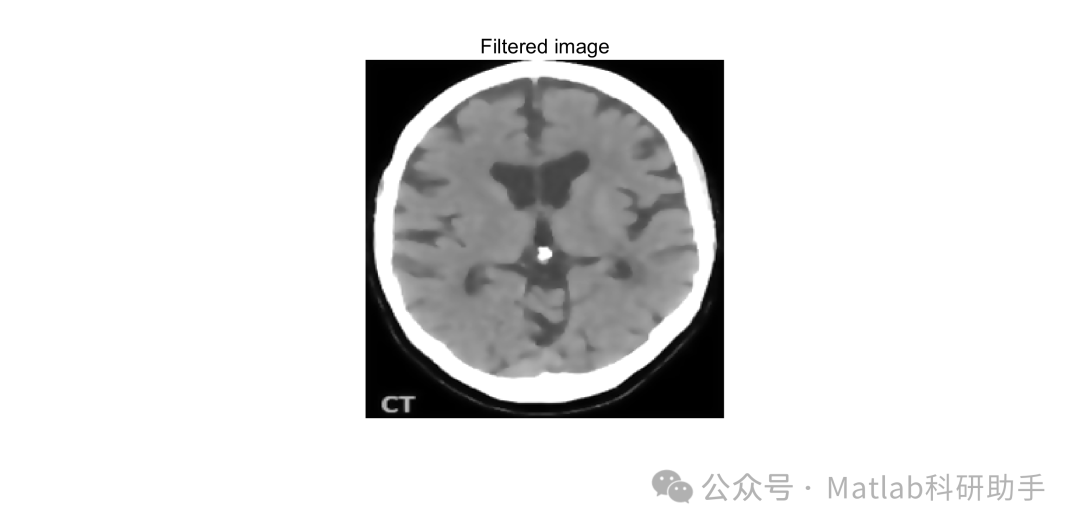

将各向异性滤波器应用于 MRI 图像,能够有效去除噪声,同时保持脑肿瘤和正常组织的边缘 。在去除噪声方面,它可以平滑图像中因成像设备或环境因素产生的随机噪声,使图像更加清晰 。对于脑肿瘤区域,由于肿瘤边界处的梯度较大,各向异性滤波器能够避免过度平滑,保留肿瘤的边缘信息,为后续的肿瘤分割和特征提取提供更好的图像基础 。例如,在 T2 加权像中,经过各向异性滤波处理后,肿瘤组织与周围水肿区域的边界更加清晰,有利于准确区分肿瘤和正常组织 。

首先,对原始 MRI 图像进行各向异性滤波预处理,去除图像中的噪声,增强图像的边缘和细节信息 。然后,选择合适的图像分割方法对滤波后的图像进行分割 。如果 MRI 图像的灰度分布较为简单,可优先尝试基于阈值的分割方法;对于灰度分布复杂的图像,可采用基于区域的分割方法或基于深度学习的分割方法 。在分割过程中,可根据实际情况结合多种分割方法,如先使用阈值分割进行初步分割,再利用区域生长法对分割结果进行优化,或者将深度学习模型的分割结果与传统方法相结合 。最后,对分割得到的肿瘤区域进行后处理,如去除小的噪声区域、填充空洞等,得到最终的脑肿瘤检测结果 。

⛳️ 运行结果